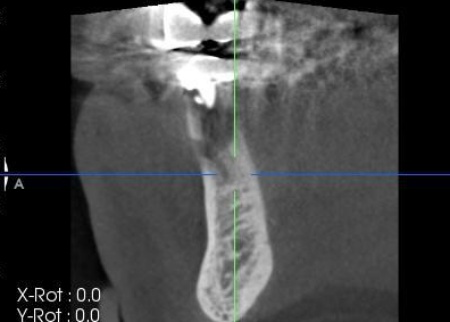

| 行ったご提案・治療内容 | まずは左下奥歯に装着されていた被せ物を慎重に除去し、歯根の状態を直接確認します。 その結果、歯根破折が明確に認められたため、歯の温存は困難であると判断しました。 抜歯後の治療として、以下2種類の方法を提案しました。 ①延長ブリッジ ②インプラント それぞれのメリットとデメリットを丁寧にお伝えしたところ、患者様は②のインプラント治療を選択されました。 まずは局所麻酔を行い、破折した歯を丁寧に抜きます。 抜歯後は骨の治癒を待つため、約3ヶ月間の経過観察を行いました。 経過観察後、骨の状態が安定したことを確認したら、インプラント体(人工歯根)を顎の骨に埋め込む手術を行います。 手術では、歯茎を切開した骨を露出させ、専用の器具で慎重に穴を形成したうえでインプラント体を埋入します。続いて歯茎を縫合し、インプラント体が骨と結合するまでの期間を設けました。 後日、インプラント体と骨がしっかりと結合したタイミングで、インプラント体の上に土台を装着し、人工の歯を取り付けます。 最後に、装着したインプラントの見た目や使用感、噛む機能の回復などを確認して、治療を終了しています。 |

抜歯後の骨の状態を確認しています。

インプラントの埋入設計をしました。